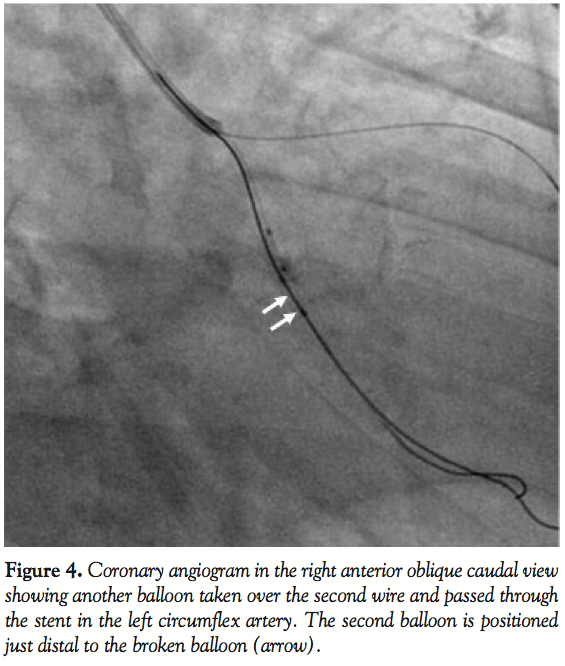

Case Report. A 65-year-old, diabetic male patient presented with inferior wall myocardial infarction (MI) and intractable post-MI angina. Coronary angiogram demonstrated significant double-vessel disease in the left circumflex (LCX) (Figure 1) and right coronary artery (RCA). He was taken for percutaneous transluminal coronary angioplasty with stenting to the LCX. The left coronary artery was engaged with a Judkins left guiding catheter (GC) (Medtronic Vascular, Santa Rosa, California). The lesion was crossed with a Stabilizer Plus